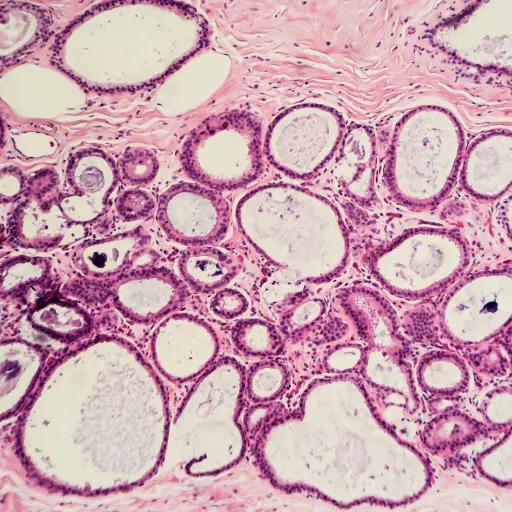

乳房纤维囊性的

“有些女性有肿块乳腺组织,称为纤维囊肿乳房,在本月的某些时期可能会更加痛苦,”康博士说。Bhanote说,这些肿块通常不是癌症,而是囊肿充满液体,这可能会在激素变化中变得扩大和痛苦。“如果疼痛仍然存在并且无法解决,或者在普通乳房组织外面触发坚定或不规则的肿块,您应该与您的提供商联系以进行进一步评估,”kang博士说。